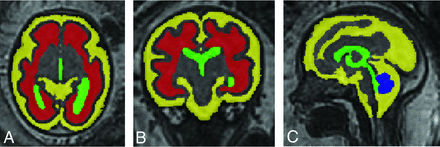

Conversely, our study demonstrates that fetuses with CDH have indications of atypical brain development, ie, with a significant delay at 28 and 33 weeks of gestation (Fig 3). By 33 weeks, the quantitative scores were in the normal range. However, quantitative scoring was performed on primary and not on secondary sulci, limiting the detection of subtle folding abnormalities.30 The qualitative scoring system we used allows a thorough scoring of brain sulcation throughout a wide GA range, because it evaluates the primary formation as well as the presence of secondary and tertiary sulcation.20 We were not able to compare our morphologic findings with the postnatal clinical neurobehavioral assessment. In infants with CDH, 9% (4%–14%) have abnormal opercularization, which translates later into language and speech abnormalities.7 In our study, grading of the operculum was significantly lower at the first time point and at the second time point, though only left-sided. It remains unclear whether the abnormalities we found are related to any of the reported functional consequences observed in infants with CDH or other abnormalities. In earlier studies, scores using the same system correlated well with the Neonatal Behavioral Assessment Scale,31 though this correlation was in fetuses with isolated nonsevere ventriculomegaly or late-onset growth restriction.14,22 The functional impact of our observations in fetuses with CDH remains to be elucidated. Moreover, one must take into account that any abnormality observed postnatally may as well have been acquired after birth.

Three orthogonal T2-weighted spin-echo images in a healthy fetus (A–C) and a fetus with a left-sided diaphragmatic hernia (D–F), both at a GA of 30 weeks 4 days. In the axial plane (A and D), the enlarged pericerebral space is evident (arrowheads). The difference in gyrification is most evident in the parietal area and best seen in the coronal plane (circle in B and E) and to a lesser extent in the sagittal plane (arrows in C and F). The enlarged pericerebral space in the coronal and sagittal planes is marked with arrowheads.